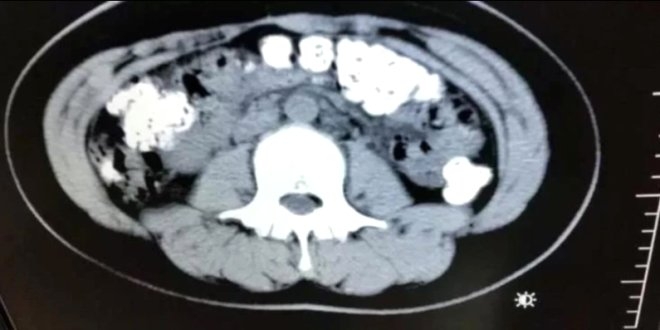

14 yaşındaki kıza tedavi uygulandı ve sindirim sistemini tıkayan toplardan kurtulması sağlandı.

Çin'de 14 yaşındaki Xiao Shen, 4 gün boyunca kabızlık çekince hastaneye kaldırıldı. Midesinden öyle bir şey çıktı ki doktorlar bile şoke oldu.